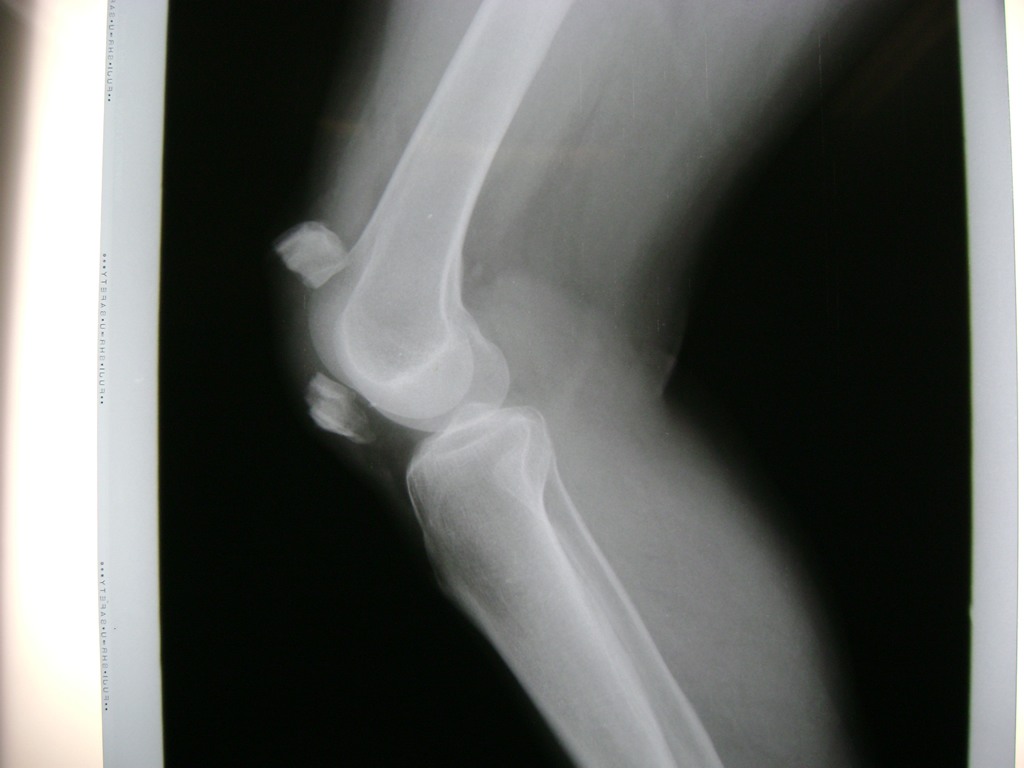

Cirugías de Codo - Rodilla

La artroscopia de rodilla es un cirugía en el cual la estructura interna de la articulación es examinada ya sea para realizar un diagnostico o para realizar un tratamiento, este procedimiento se realiza utilizando un instrumento parecido a un pequeño tubo llamado artroscopio.